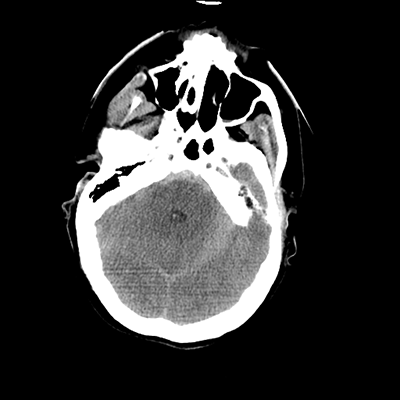

CTA head/neck

With the CTA of her head/neck, we can sort of see some atherosclerosis (though the images aren't windowed well for this). Importantly, though, we can see a rounded abnormality around the tip of the basilar/left PCA. This is an aneurysm! This helps put things together. This patient had an aneurysmal rupture leading to SAH and hydrocephalus, causing her loss of consciousness. While her leg extensor movements could be seizures, they're probably actually posturing movements, secondary to intracranial hypertension in the setting of her hydrocephalus.